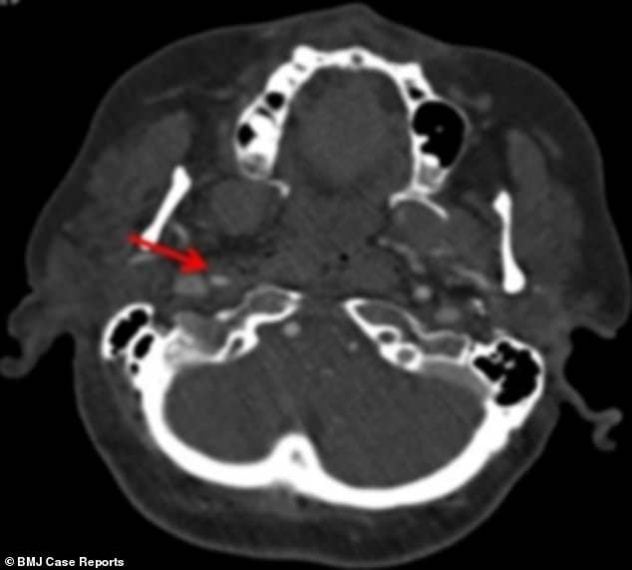

La scansione cerebrale mostra l'arteria ispessita e quindi indebolita

Dopo essere stata travolta da un'onda in vacanza, per una turista irlandese sono iniziati seri problemi. La donna, 60 anni, ha iniziato a soffrire di mal di testa e dolori al collo, oltre che fastidi alle palpebre e alle pupille. Le scansioni cerebrali hanno mostrato che l'urto dell'onda aveva provocato la rottura di vasi sanguigni e di un'arteria nel collo che porta sangue al cervello. I medici, sbalorditi, hanno pubblicato il racconto in una rivista medica e dichiarando che si trattava del primo caso di questo genere. Alla paziente è stata diagnosticata la rara condizione della sindrome di Horner, secondo il racconto pubblicato su BMJ Case Reports. Una condizione causata da danni ai nervi del viso e risultati nella bulbo oculare che affonda nella sua cavità. All'ospedale della Galway University, i medici hanno scoperto che gli occhi della paziente si muovevano involontariamente, ma era comunque in buona salute. Dopo aver assunto inizialmente l'aspirina per evitare l'ictus, la paziente è pienamente guarita sei mesi dopo.